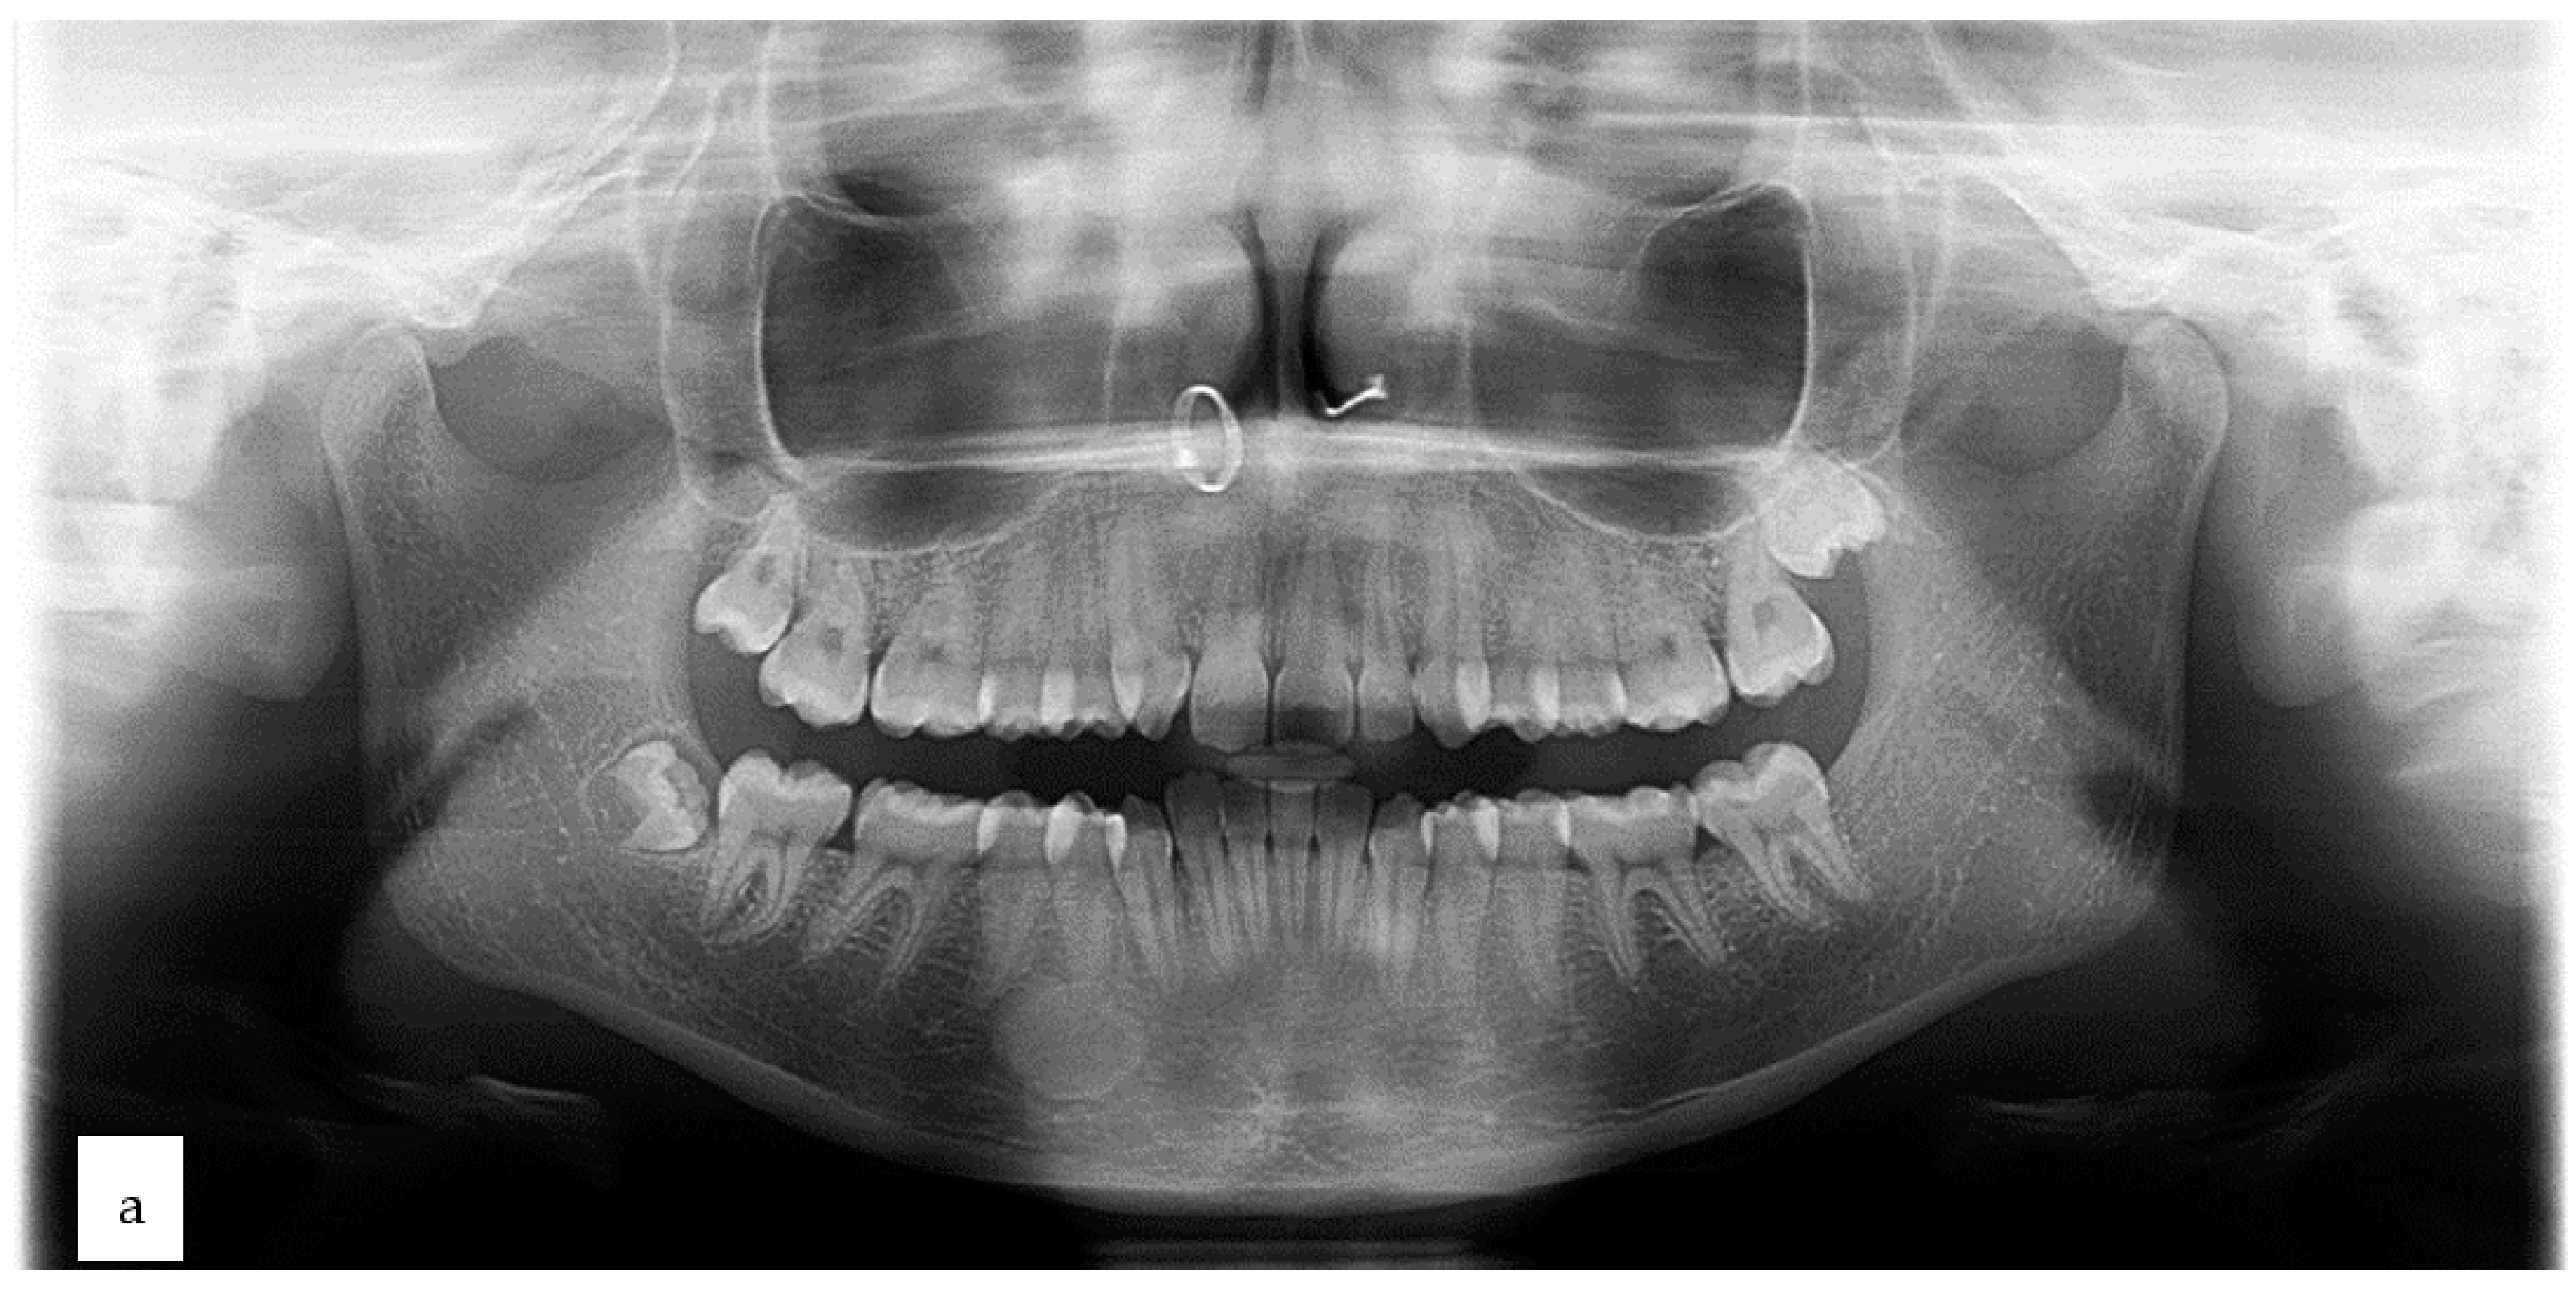

2. Case Presentation